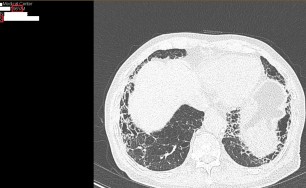

이런 형태의 기침은 엑스레이상 정상인 경우가 대부분입니다.

숨케어한의원에서는 전화예약을 받고 있습니다. 내원시 엑스레이, CT사진, 폐기능검사지를 가지고 오시면 자세한 상담이 가능합니다.